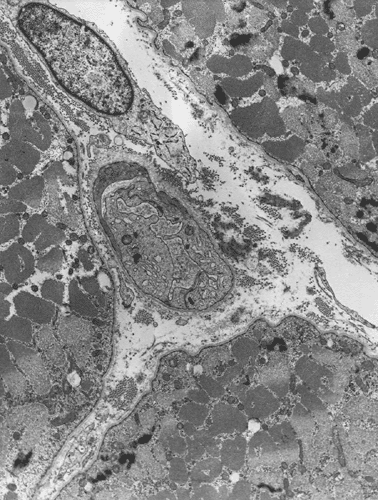

Diagnostic procedure

A biopsy was performed. The followings are representative photomicrographs of the biopsy material.

Pathology of the case:

| G. | H. | I. | J. |

What is your diagnosis? Discussion